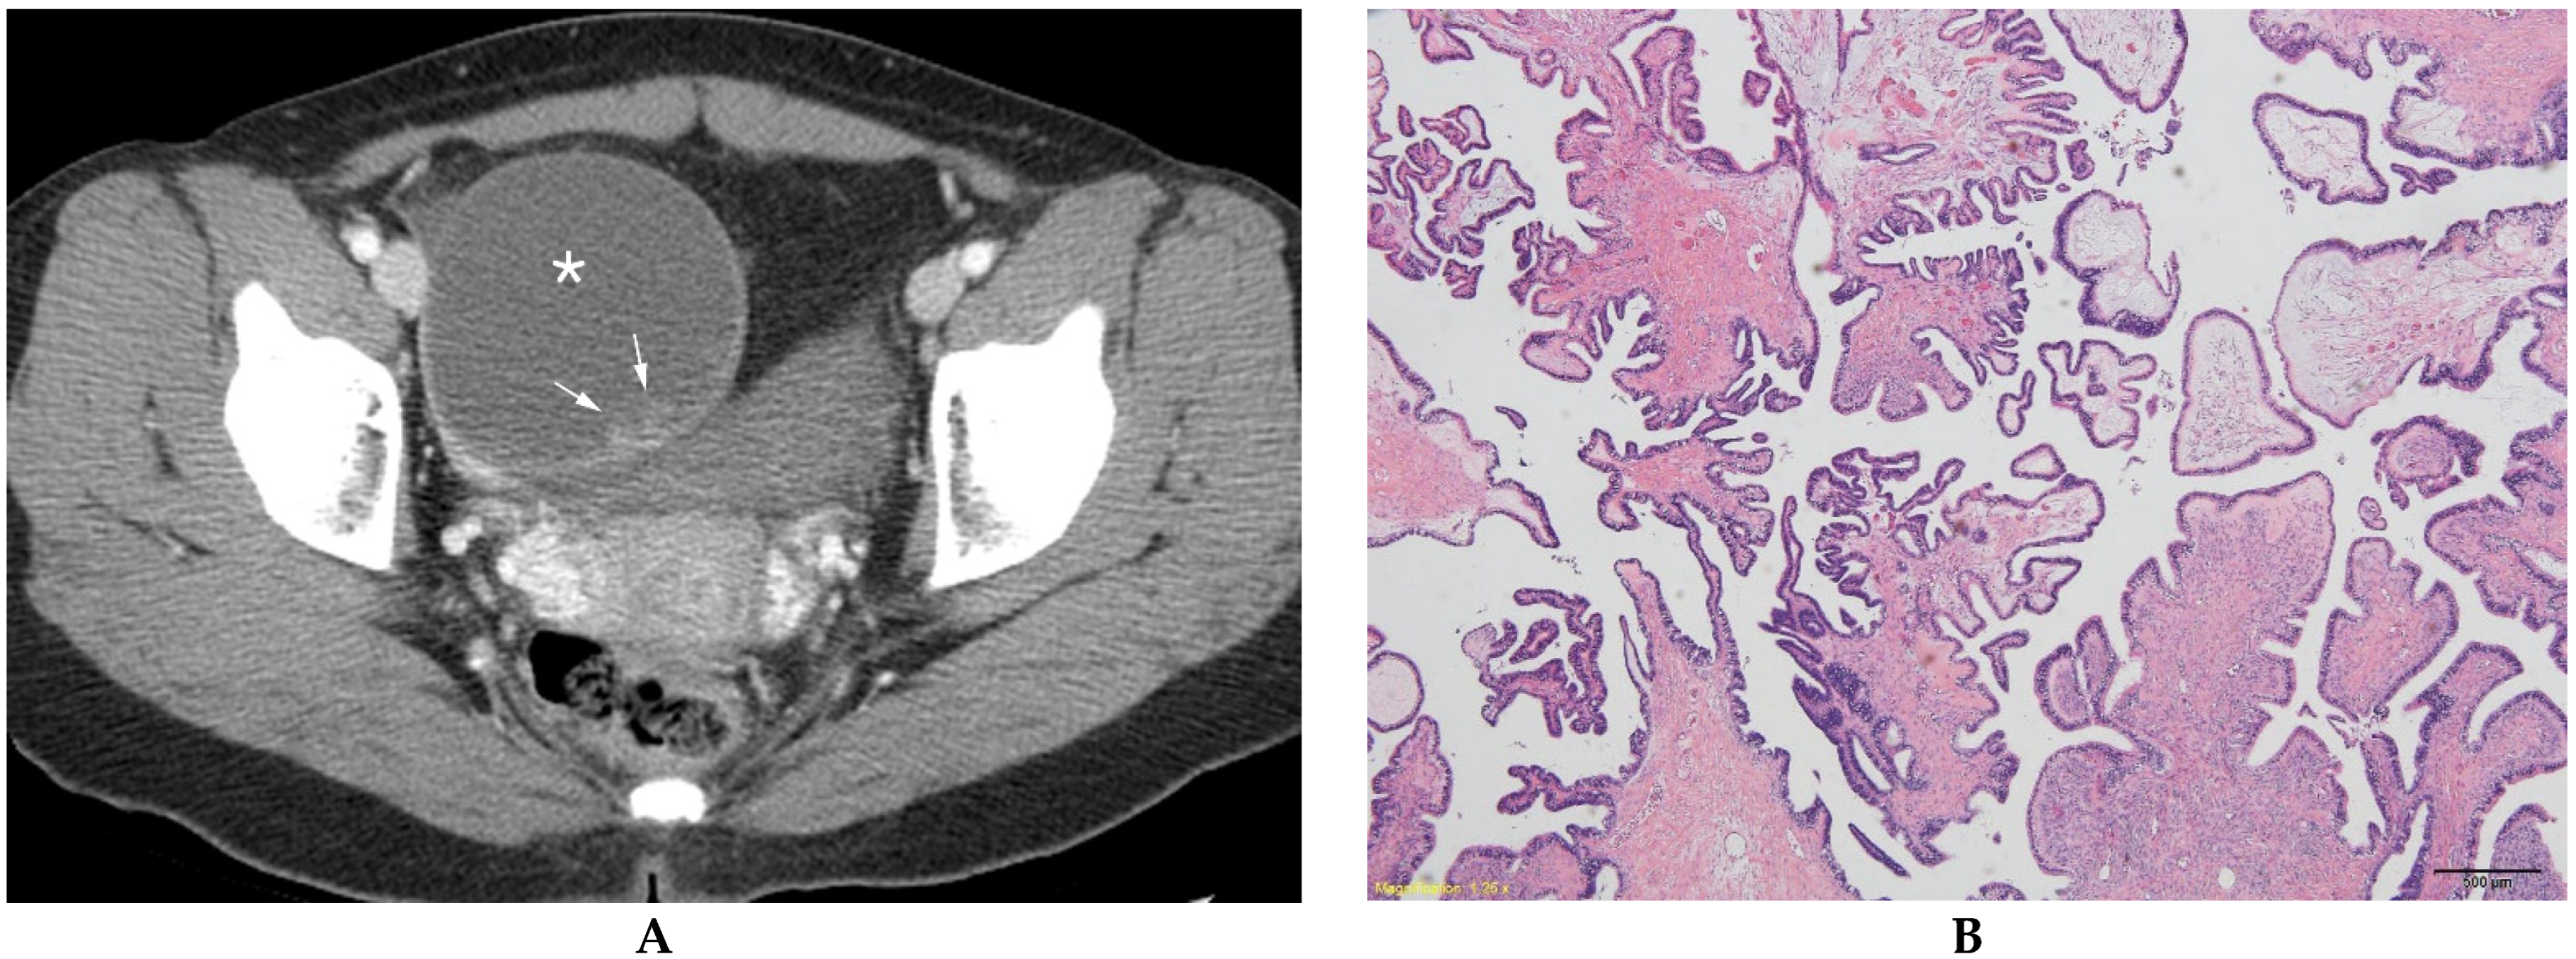

Figure 2.

Serous borderline ovarian tumor in a 27-year-old woman. (A) Contrast-enhanced axial CT shows a unilocular cystic mass (*) with an ill-defined solid component (arrows) in the right ovary. (B) Microscopically, tumor cells present nuclear atypia and cellular proliferation without stromal invasion (hematoxylin and eosin 40×).